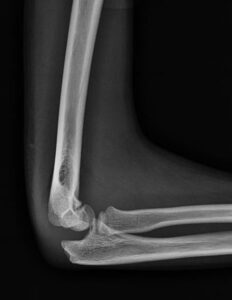

[toggle title=”Anterior Humeral Hat” state=”close”]

Lateral grafide humerus ön yüzeyine paralel ve bitişik çekilen çizgi kapitulumun 1/3 ortasından geçmelidir.

Bu hattın öne ya da arkaya yer değiştirmesi suprakondiler humerus kırığını destekler.

Aynı zamanda suprakondiler kırık hattıyla beraber posterior yağ yastıkçığı bulgusu da görülmekte

Bununla beraber kırık hattı ve posterior yağ yastıkçığı bulgusu da seçilmekte.

[box type=”info” align=”” class=”” width=””]Ancak yapılan çalışmalar <2.5 yaş çocuklarda kapitulumun küçük boyutu nedeniyle kırık olmayan normal grafilerde de anterior humeral hattın kapitulum önünden geçtiği görülmüş. Bu yüzden >2.5 yaş çocuklarda değerlendirilmesi daha doğru sonuçlar vermekte.[/box][/toggle]